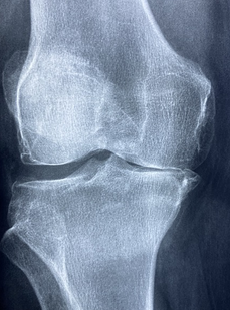

무릎 염증은 무릎 관절에 염증이 생기는 상태로, 통증, 부종, 발적, 뻣뻣함 등의 증상을 유발합니다. 무릎 염증의 원인은 다양하지만, 대부분 골관절염, 외상 후 관절염, 류마티스 관절염 등의 질환과 관련이 있습니다. 무릎 염증을 치료하는 방법은 원인에 따라 다르지만, 일반적으로 다음과 같은 방법들이 있습니다.